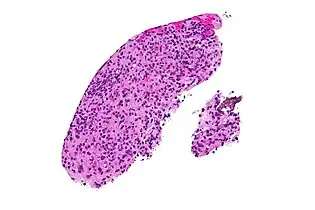

High magnification micrograph of toxoplasmosis

Brain biopsy-High magnification micrograph of toxoplasmosis

Real-time PCR is useful in pathogen detection, gene expression and regulation, and allelic discrimination. This PCR technique utilizes the 5' nuclease activity of Taq DNA polymerase to cleave a nonextendible, fluorescence-labeled hybridization probe during the extension phase of PCR.[63] A second fluorescent dye, e.g., 6-carboxy-tetramethyl-rhodamine, quenches the fluorescence of the intact probe.[63] The nuclease cleavage of the hybridization probe during the PCR releases the effect of quenching resulting in an increase of fluorescence proportional to the amount of PCR product, which can be monitored by a sequence detector.[63] Lymph nodes affected by Toxoplasma have characteristic changes, including poorly demarcated reactive germinal centers, and scattered epithelioid histiocytes.[64]